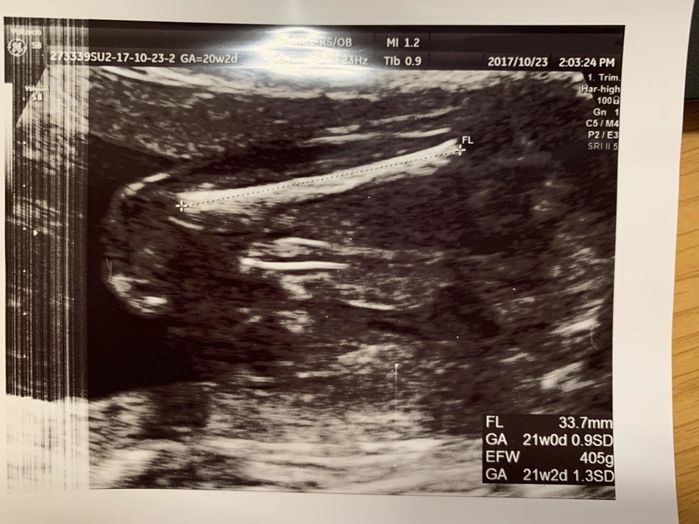

妊娠20週目 胎動を感じながら過ごす日々

妊娠20週目。私の体も妊娠に慣れてきたのか、おなかが大きくなるスピードがとても速く感じられました。妊娠20週からは健診の時に、推定体重も教えてもらえるようになりました。この頃から、会社の同僚や保育園のママ友からも「おめでたですか?」と聞かれることが増えてきました。妊娠5ヶ月の中ごろから始まった胎動が、ずいぶんと激しくなり、「妊娠10ヶ月までおなかが持つかしら…?」と思うほどで、少し心配になっていました。